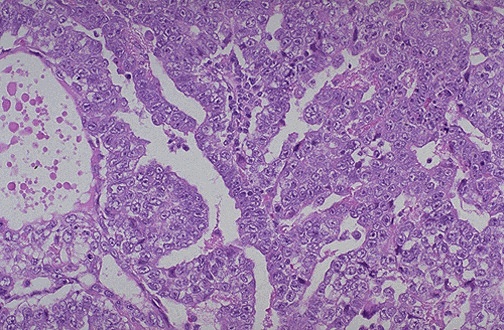

This is the histologic pattern of an embryonal carcinoma. Sheets of blue cells are trying to form primitive tubules.